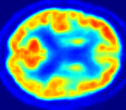

Looking at sample synthetic PET images in Fig. 3, it can be seen that all of the models are able to make reasonable predictions. The outputs of the U-PET and U-PET (no att.) look very similar and are smoothed compared to the input. The pix2pix predicts more details, which seem to be important for the discriminator. However, even though this model has finer predictions, the intensity values are worse compared to the U-PET and U-PET (no att.) as seen in Fig. 2; an example is given in Fig. 3 in the second row.

From a clinical perspective, the synthetic generated PET show a smoother version of the real PET images but keep the same pattern of FDG uptake, especially, hypometabolism in the respective brain areas. This backs up our hypothesis, that MRI contains information that correlates with the functional information of PET images. Moreover, the synthetic PET could be used as complementary visualization for physicians beyond the task of classification.

| MRI | PET | Synthetic PET | AttMap skip | AttMap |

In Fig. 4, the attention maps of the U-PET are shown for multiple examples. On the one hand, the attention map of the skip connection (AttMap skip) highlights details of the brain structure, which is in agreement with the assumption that the network has to transform the specific structures of the MRI scan into the PET modality. On the other hand, the attention gates used for the classification task rather focus on more specific regions. One can observe a trend that the attention maps used for classification tend to highlight regions which have a low uptake in the PET. Since areas with a lower uptake in the PET correspond to areas with lower functional activity (hypometabolism), this focus area of the network seems reasonable with respect to the classification task.